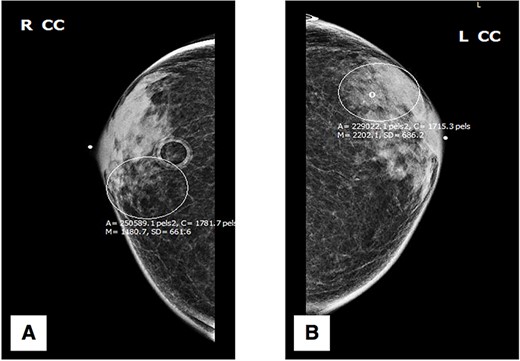

Initial physical exam was notable for bilateral gynecomastia with expression of scant serous fluid on palpation. Negative findings included any ‘active nipple’ discharge, presence of bleeding, breast tenderness, palpable masses or architectural abnormalities. The patient was referred for further diagnostic workup, beginning with digital mammography. Standard craniocaudal (Fig. 1) and mediolateral oblique (Fig. 2) views of bilateral breasts were performed, which revealed pleomorphic calcifications in the upper outer quadrant of the left breast, as well as amorphous calcifications in the lower inner quadrant of the right breast, consequently affording the patient a Breast Imaging Reporting and Data System score of 4 (suspicious for malignancy) with recommendation for subsequent biopsy.

Craniocaudal (CC) mammography: (A) right breast; (B) left breast.